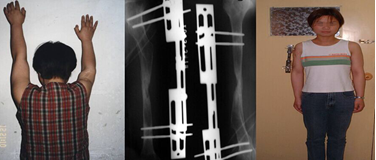

病例5:蔡某,女,28 岁。儿时右肱骨骨髓炎致右上臂停止生长,较对侧短缩11cm。